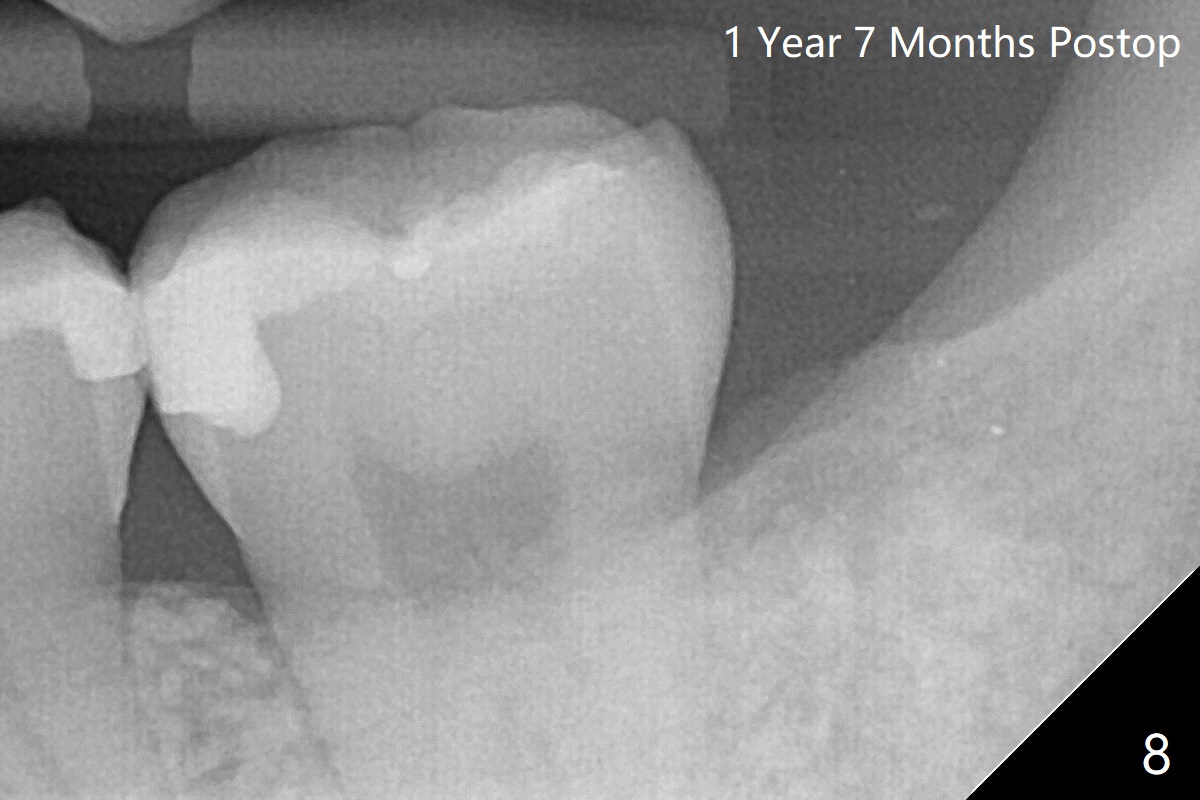

术后一年七个月外斜嵴前缘形成(图八)。